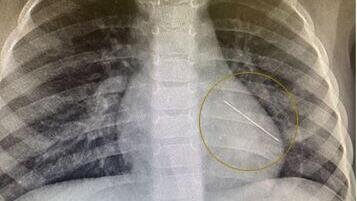

После – рентген показа, что в легких есть что-то, похожее на острый предмет. Мальчик сказал, что несчастный случай произошел с ним еще в 2021 году, но он это скрыл.

А заведующий хирургическим отделением медучреждения Глеб Новошинов говорит:

«Портновская иголка со временем капсулировалась в базальных частях органа. И к счастью доктора смогли увидеть ее, определили его пальцами. В противном случае нужно было бы просто отрезать фрагмент легкого».